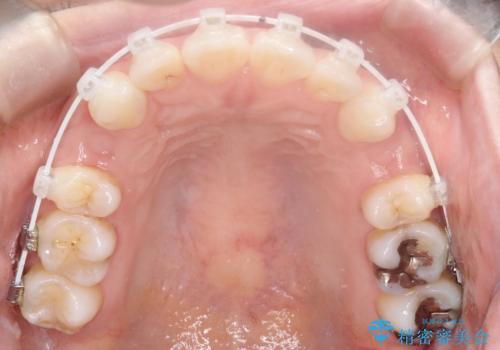

- 審美装置

- 2年1ヶ月

上下左右の歯を1本ずつ抜歯して、そのスペースを利用して口元を引っ込める計画としました。